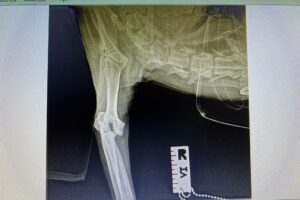

Rüde, Mischling, 3 Jahre, Vermittelt, stammt aus Italien, TierNr. 5213

Bullo

Mischling

3 Jahre

Rüde